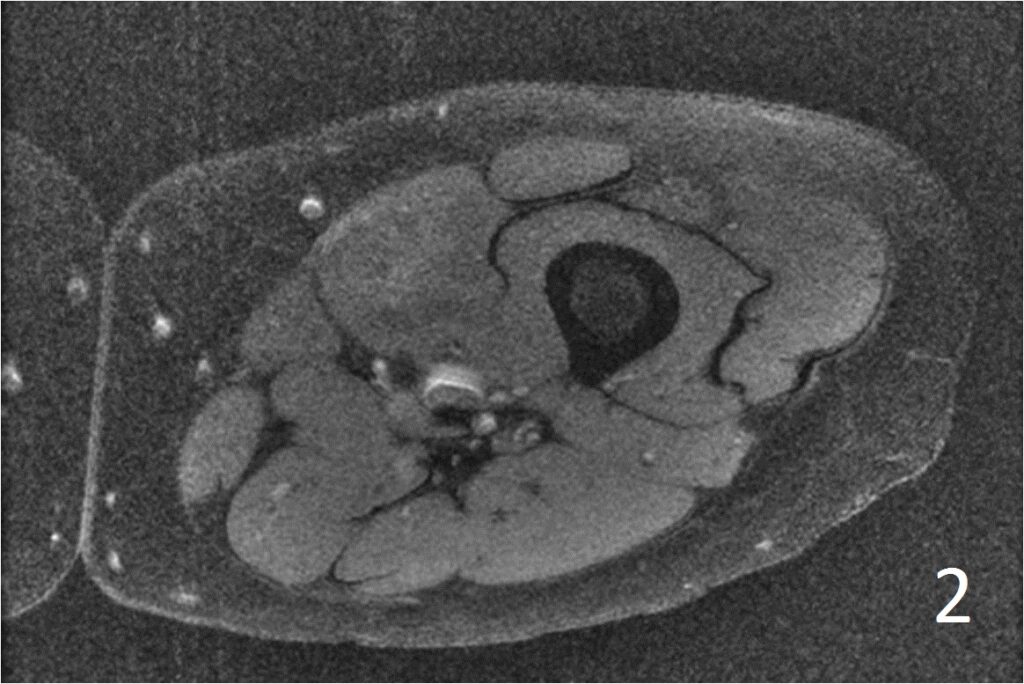

MRI

• Well defined heterogeneous mass on T1W and IR sequences (Fig. 2, 3) heterogeneous enhancement on postcontrast images (Fig. 4)

Fig. 2-4: Axial T1W FS of the thigh shows a ill-defined mass in medial thigh, and fairly well defined and heterogeneous on IR sequence (Fig. 3). Axial T1W displays a heterogeneous mass with mild enhancement post gadolinium (Fig. 4)